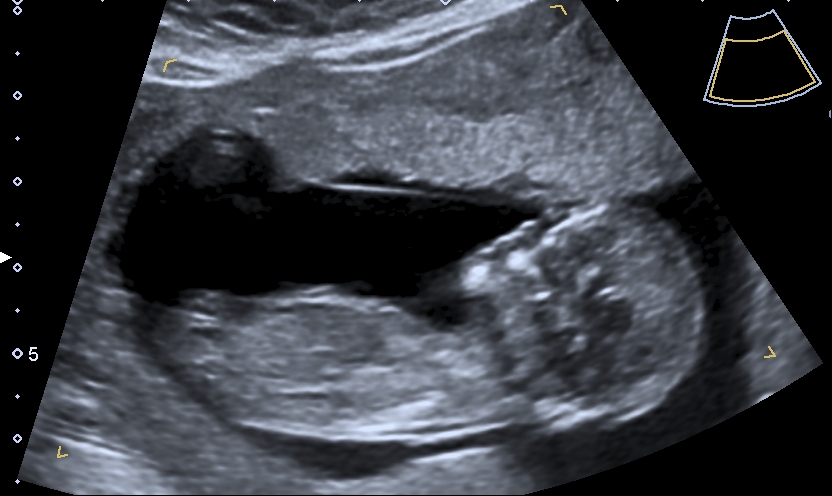

The next few days were really difficult, Nathan had to take time off work as I couldn’t cope with the school runs, I spent the weekend not doing a lot. Just trying to get as much fluid in me as I could manage. On the Sunday I went to the local small hospital in the hope that something would be done but no joy, they made a few phone calls but the end result was the same, “go home and drink more!” I shouted at her, I can’t, I’m doing everything I can but this is beyond just drinking more, why won’t anyone listen to me!? So again in tears I went home and drank more! On the Monday we had our scan. We hadn’t realised that children weren’t allowed in the room with you so to start with I had to go in alone as we had Paisley with us. I went in and laid on the bed, there it was our beautiful baby, having a little wriggle. Heart beating and legs kicking. The baby didn’t want to have photos taken and kept turning away and then when she was trying to measure to date the pregnancy – the baby kept tucking it’s chin into its chest, she had me jumping and shaking my hips to try and get the baby to change position but no joy so I was told to empty my bladder, I giggled as I walked through the waiting room to the toilet, Nathan had been waiting to know if everything was ok, I told him it was but the baby was being naughty and not cooperating so I had to wee and see if that would help. I went back into the room, this time Nathan and Paisley came too. She finally got all the pictures she needed, I asked about the sac and she said it was completely regular and she would never had known it hadn’t been if I hadn’t told her, this was a massive relief! I asked if she could see anything wrong with the baby and she said no, the baby was fine and she showed us the heart beating away, I thought to myself I bet it’s a boy, I’m sure the girls heartbeats were faster than that (I wish I had said it and not just thought it!) Next she showed us the side profile, the baby’s face looked flat, I thought it was just a funny angle (another thing I wish I had questioned) we were measuring at 12weeks and 1 day, our official due date was 02-06-19! We were in “the safe zone” I really was having a baby, we made it past 12 weeks, we could now make it Facebook official! And we did, as soon as we left the hospital! We were so happy, our cheeky, naughty, beautiful little baby! Already fitting in so well with our other cheeky children!